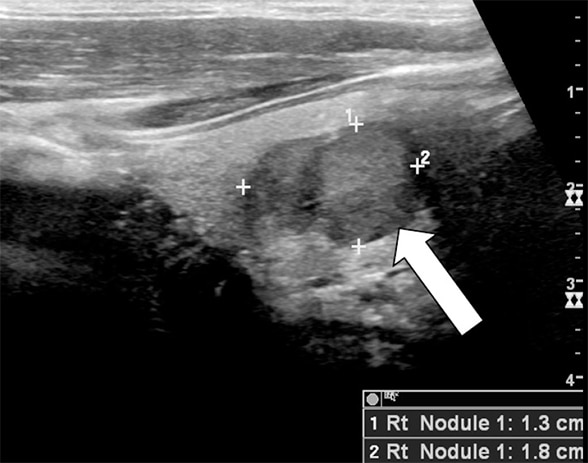

Ultrasound of the thyroid showed a 1.8-cm suspicious nodule in the midright thyroid lobe. Fine-needle aspiration biopsy findings were consistent with medullary thyroid carcinoma (MTC). Bidirectional sequence analysis was performed to test for the presence of a mutation in exons 10, 11, 13, 14, 15 and 16 of the RET proto-oncogene and was negative.

Ultrasound of a 1.8-cm nodule in right thyroid lobe

Thyroid ultrasound image showing a 1.8-cm nodule in right thyroid lobe (arrow), which proved to be medullary thyroid cancer.